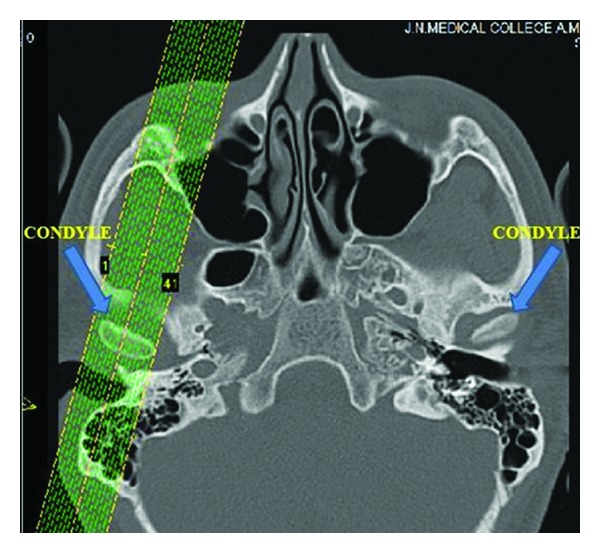

目标。本研究的目的是探讨Angle's I类正常咬合和Angle's II类1分错咬合的颅下颌关节形态和髁突在下颌窝的位置。材料与方法。本研究共40例受试者,每组20例,采用螺旋ct技术获取ct图像。各测量值采用双因素方差分析(ANOVA)进行比较,前后关节间隙变化采用配对t检验。结果。ⅰ类正常错颌中髁突前位有统计学意义(P > 0.05),ⅱ类1类错颌中髁突右位有统计学意义(P > 0.05)。结论。Angle的I类正常咬合和Angle的II类1分错的左右侧髁突和关节形态均无差异。评估髁突在各自的下颌窝的位置显示,角氏ⅰ类正常咬合患者和角氏ⅱ类1分错咬合患者的左右侧均为同心位置,且有前位的趋势。

Objective. The purpose of this study is to investigate the Craniomandibular articulation morphology and position of condyle in mandibular fossae in Angle's class I normal occlusion and Angle's class II division 1 malocclusion. Materials and Methods. The present study was conducted on 40 subjects with 20 subjects in each group, and the computed tomography images were obtained using spiral computed tomography technique. Each measurement was compared by two-factor analysis of variance (ANOVA) while changes in anterior and posterior joint spaces were done by paired t-test. Results. Statistically significant anterior positioning of condyle (P > 0.05) was observed in class I normal malocclusion, and it was significant only on right side in class II division 1 malocclusion. Conclusions. There was no difference found in the condylar process and joint morphology between right and left sides of both Angle's Class I normal occlusion and Angle's class II division 1 malocclusion. Evaluation of the position of the condyles in their respective mandibular fossae showed concentric position with a tendency towards anterior positioning for both right and left sides of the subjects with Angle's Class I normal occlusion as well as subjects with Angle's class II division 1 malocclusion.